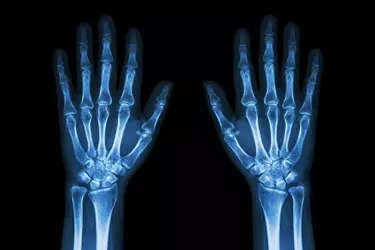

An x-ray is a noninvasive medical test that helps physicians diagnose and treat medical conditions. Imaging with x-rays involves exposing a part of the body to a small dose of radiation to produce pictures of the inside of the body.

X-rays are the oldest and most frequently used form of medical imaging. X-Rays give a lot of information about the bones within the body but the advances in X-Ray technology over the years have made it a good diagnostic tool even for soft tissue information.

The advantages of a digital radiography are many. The image procured in the digital format can be seen by the radiologist in a much better way by zooming on any part of the image. The images can be moved in 360 degree direction which helps in correct diagnosis of the problem.